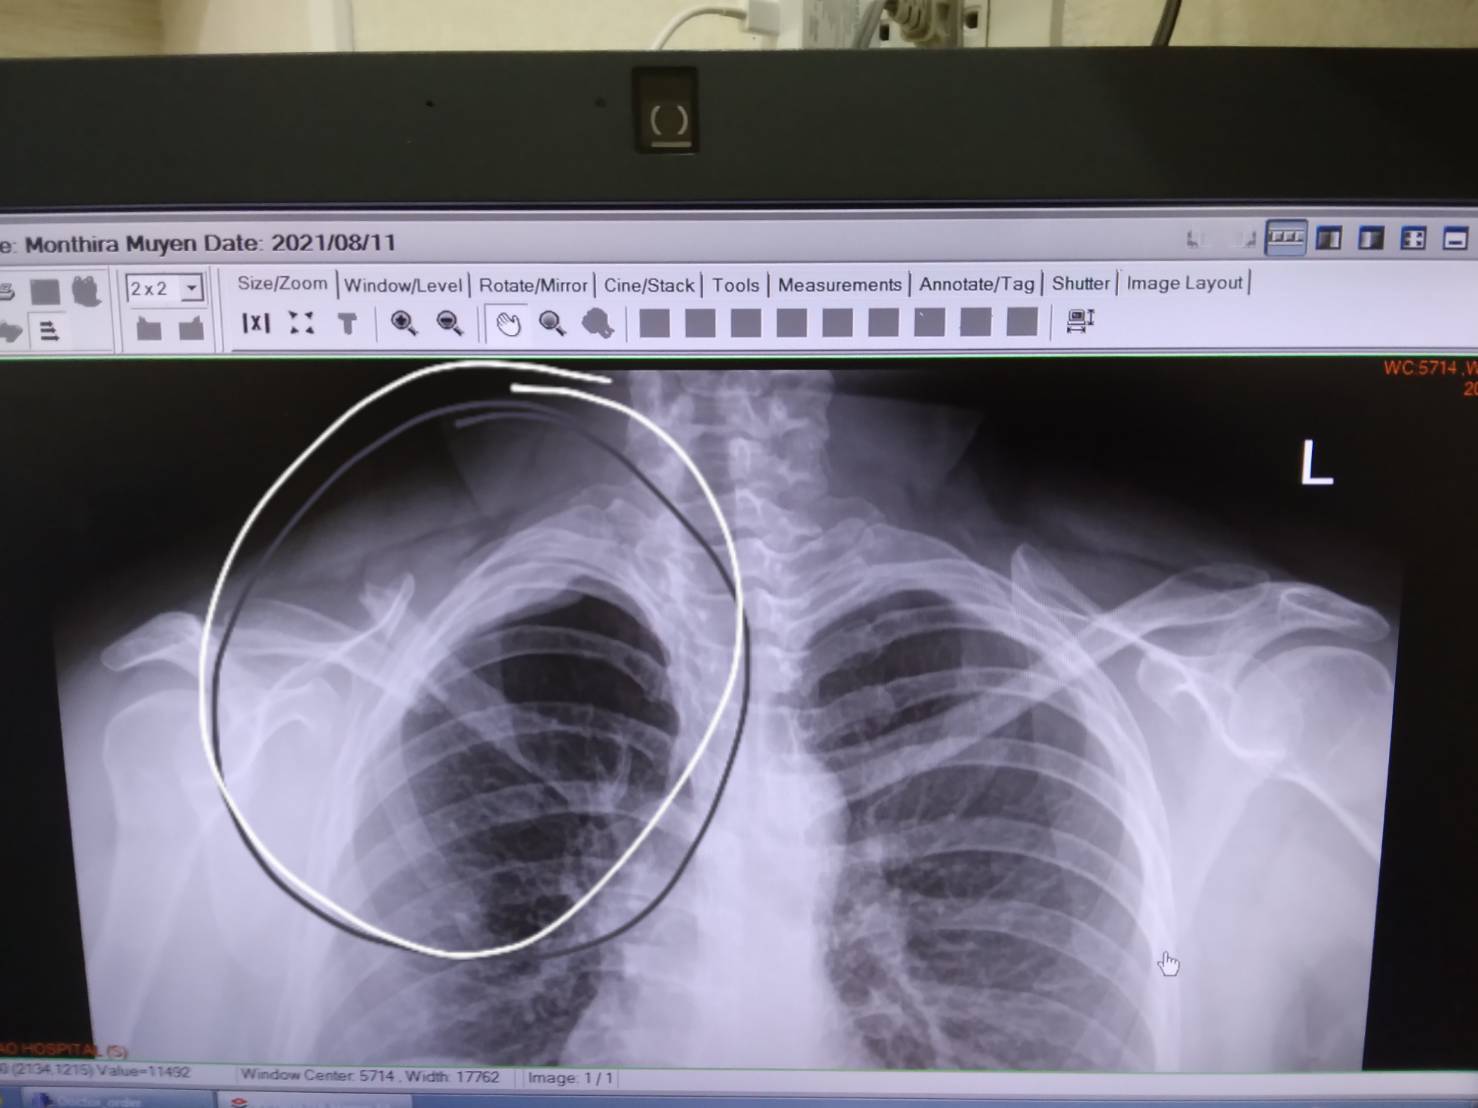

แบบนี้ต้องผ่าไหมค่ะ เครียดมากค่ะ1เดือนแล้วค่ะ